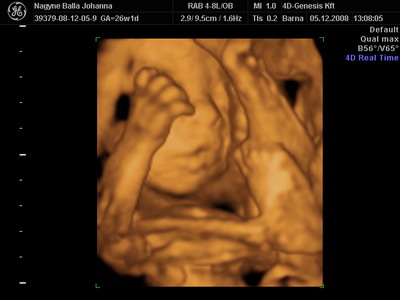

Lukács mindenkinek köszöni a dicséreteket! Én is.

Trinky! Igen, most kezd hízni Lukács. Én is... (61 kiló) Nagyon gyorsan nő a hasim. Mértem, centivel. 1,5 centi egy hét alatt. Sokat mozog, rúg nagyokat. Volt, hogy szinte feljajdultam. De ez nem panasz.